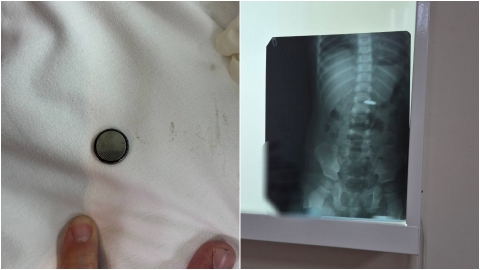

ребенок проглотил батарейку